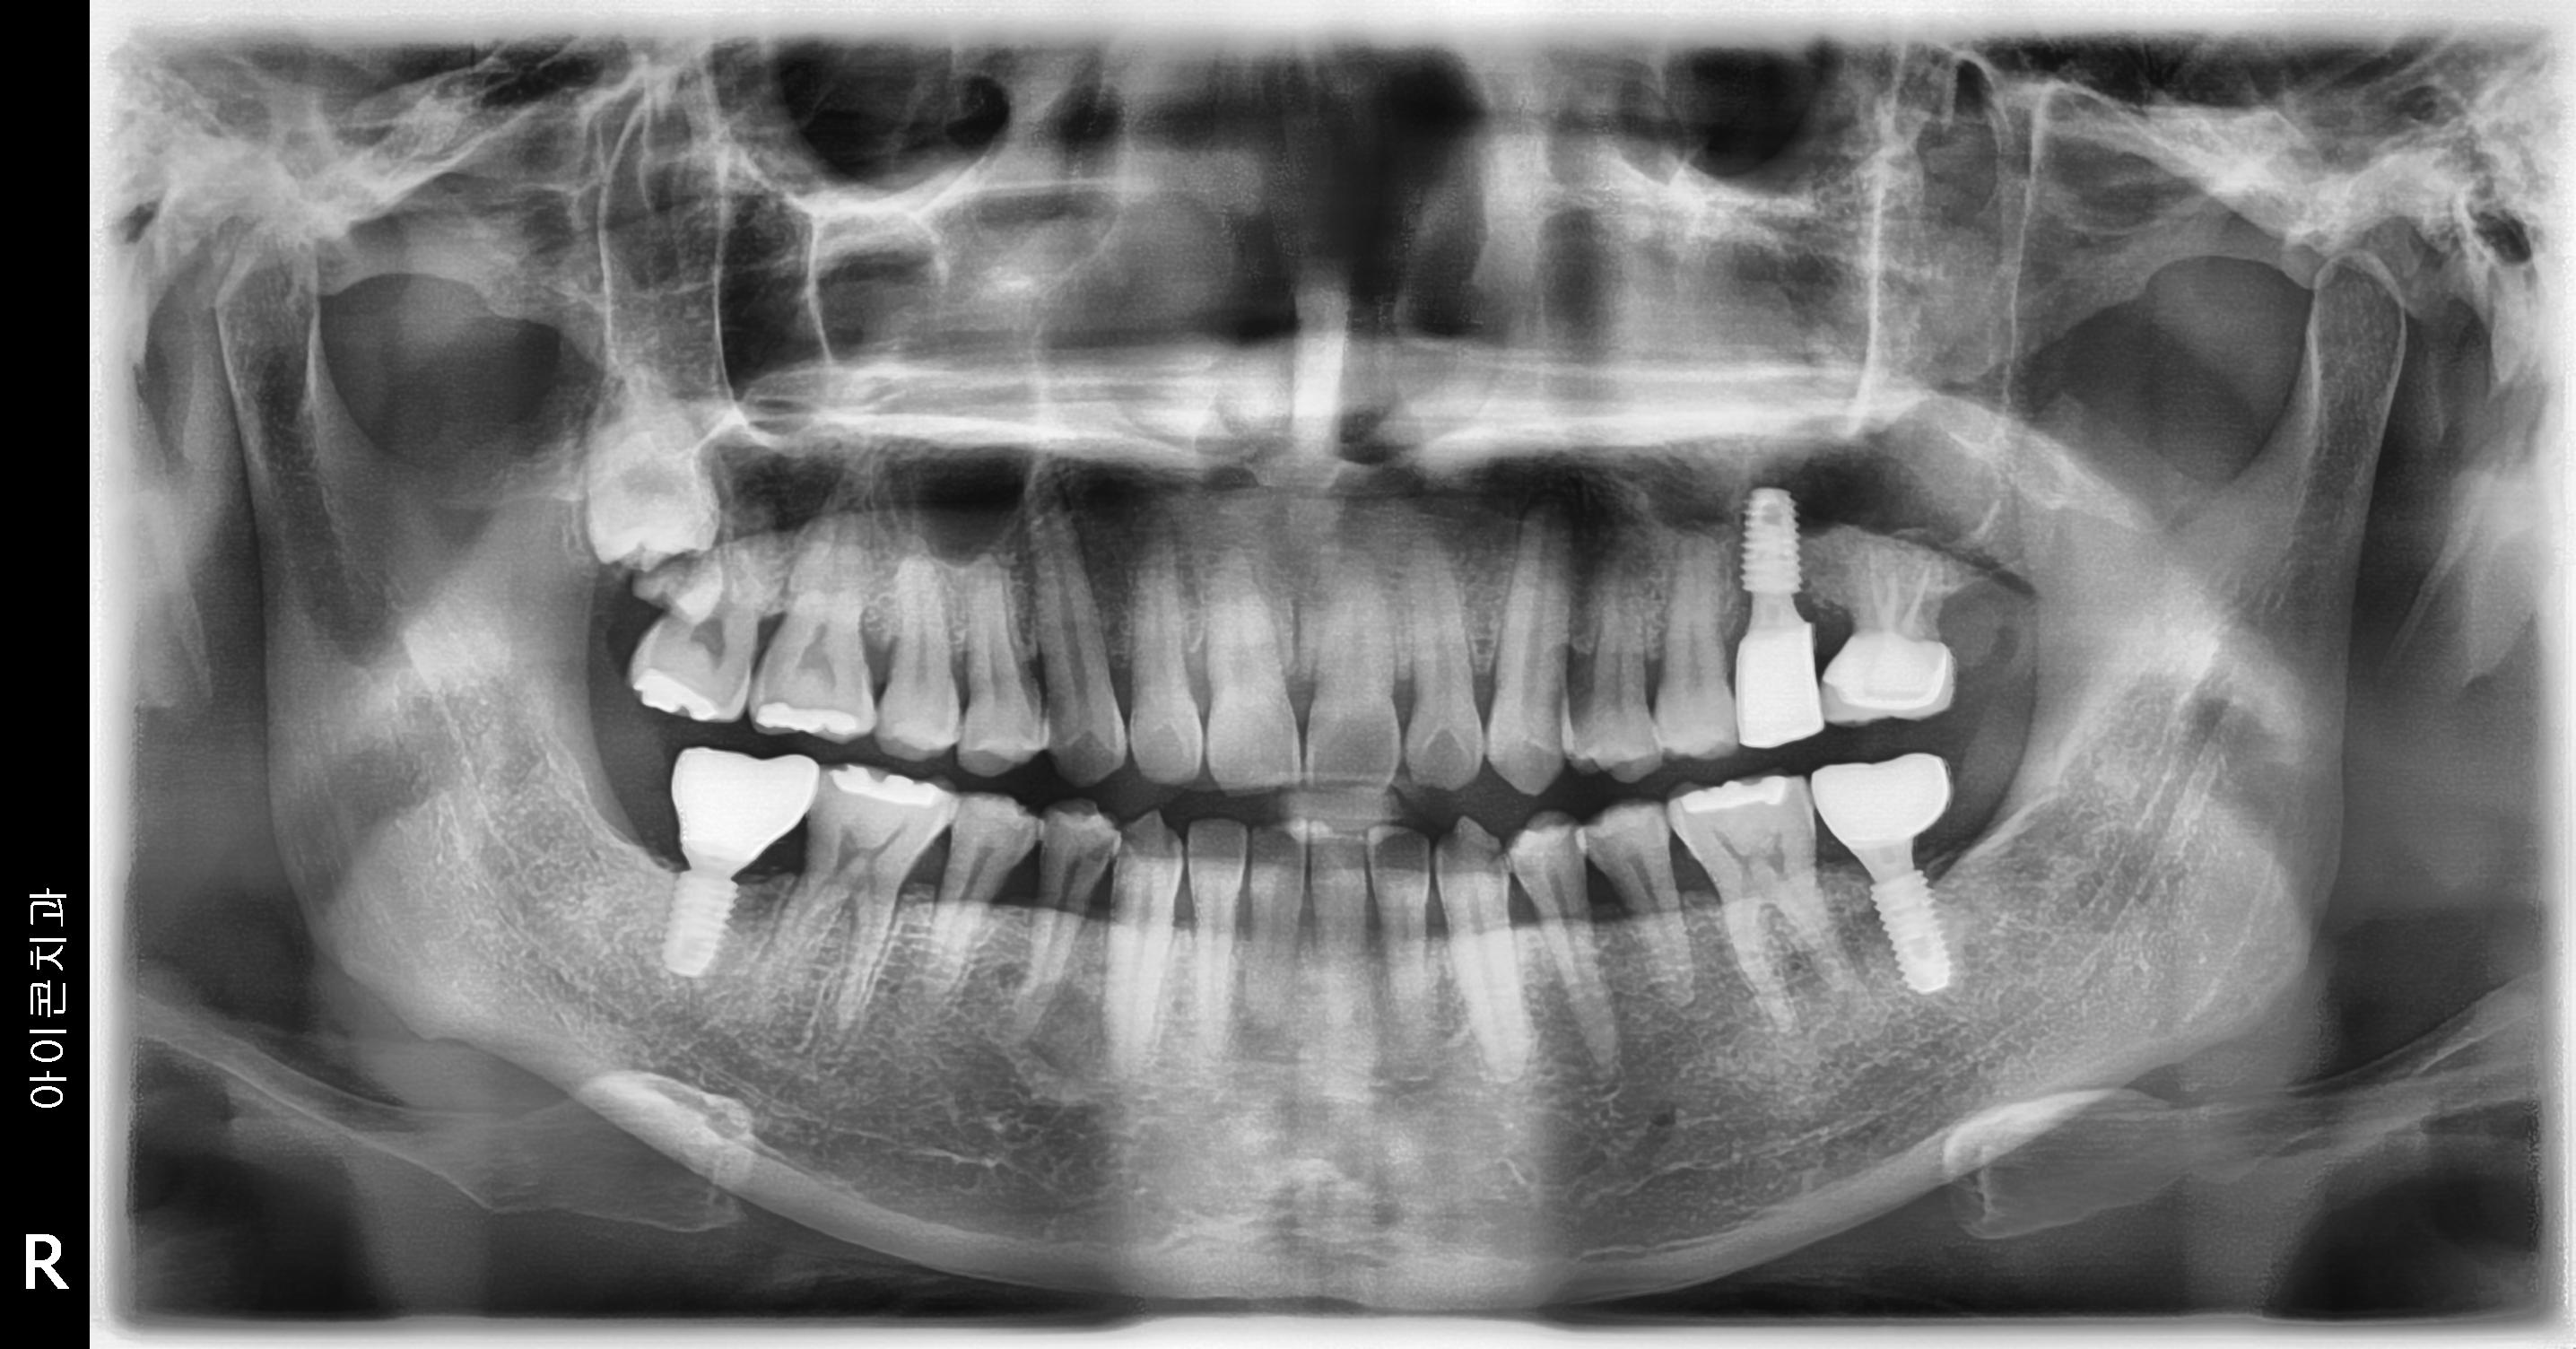

수술 전

수술 후

상하악 구치부 임플란트 식립사례

전후사진